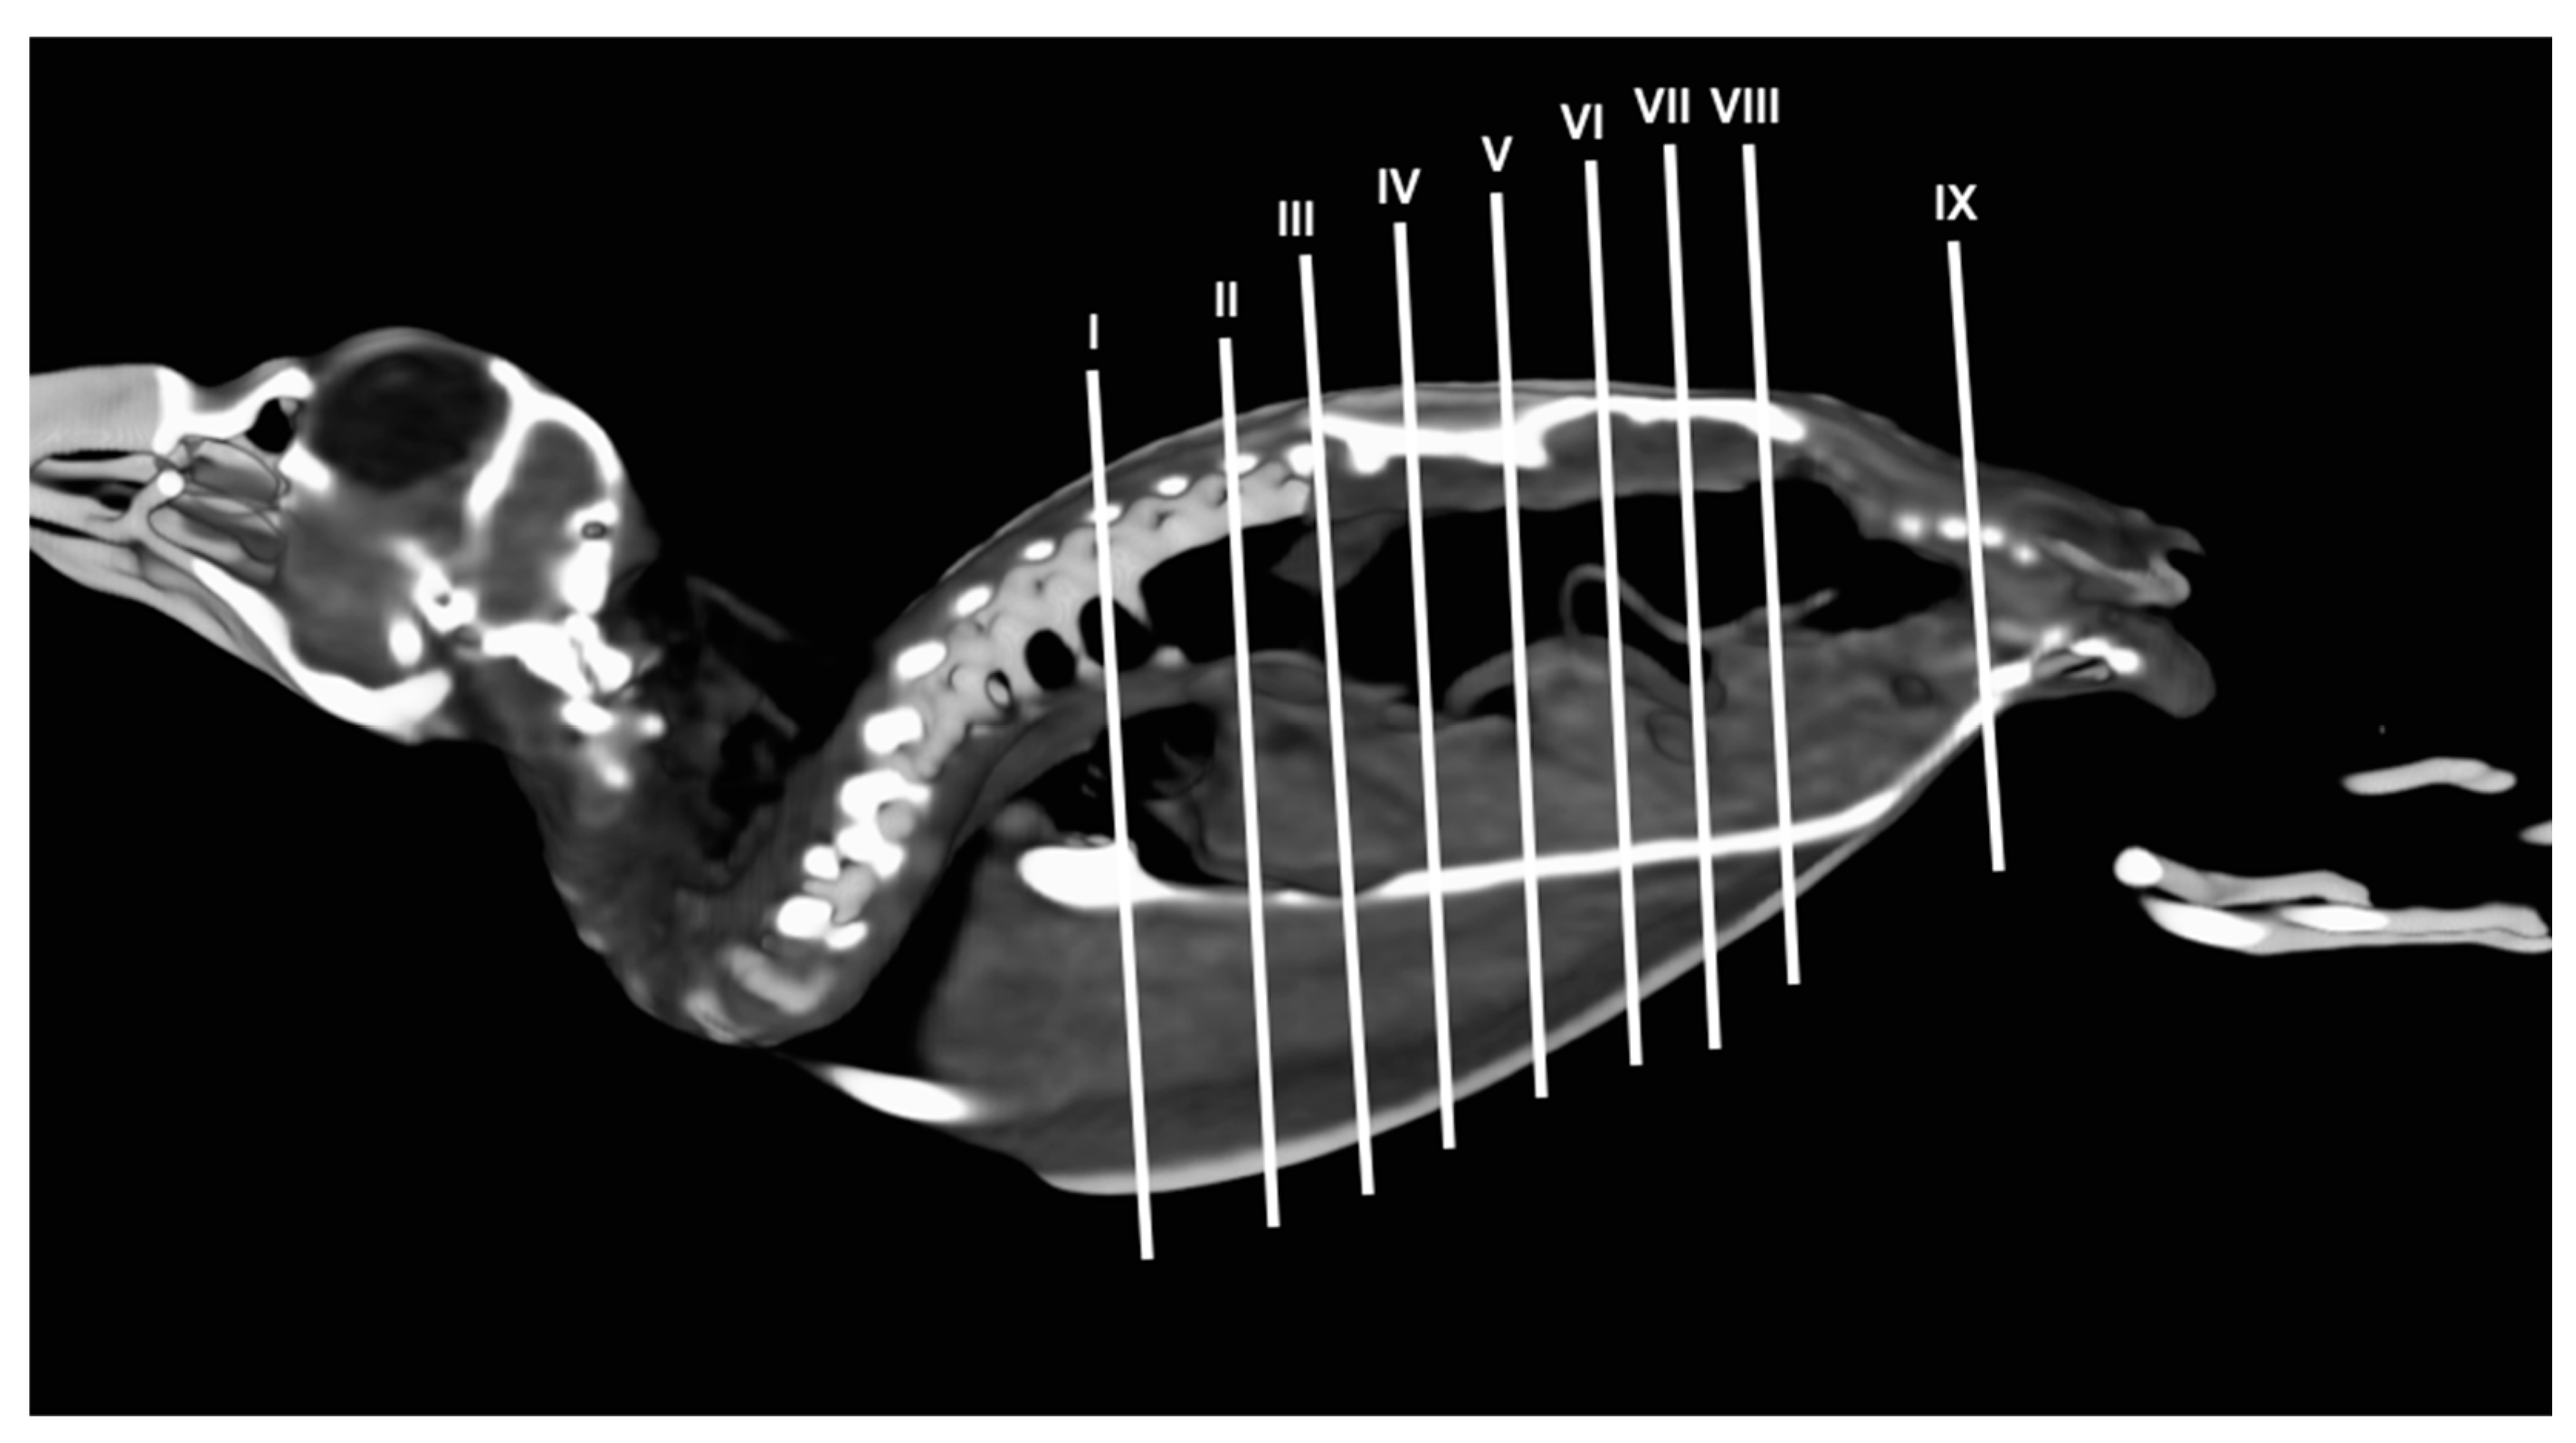

3.1. Anatomical Dissections and Cross-Sections

3.2. Computed Tomography Images